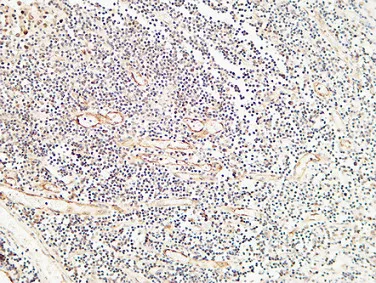

E-Selectin Rabbit Polyclonal Antibody

Cat: APRab10626

Endoglin Rabbit Polyclonal Antibody

Cat: APRab10463